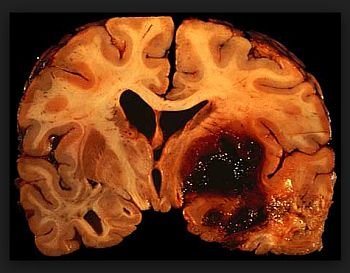

Stroke: Causes, Symptoms, and Recovery What is stroke? HEMATOMA ENLARGEMENT Intracerebral...

Hemorrhagic Stroke Diagnosis and evaluation Intracerebral hemorrhage (ICH) (Doctor only)...